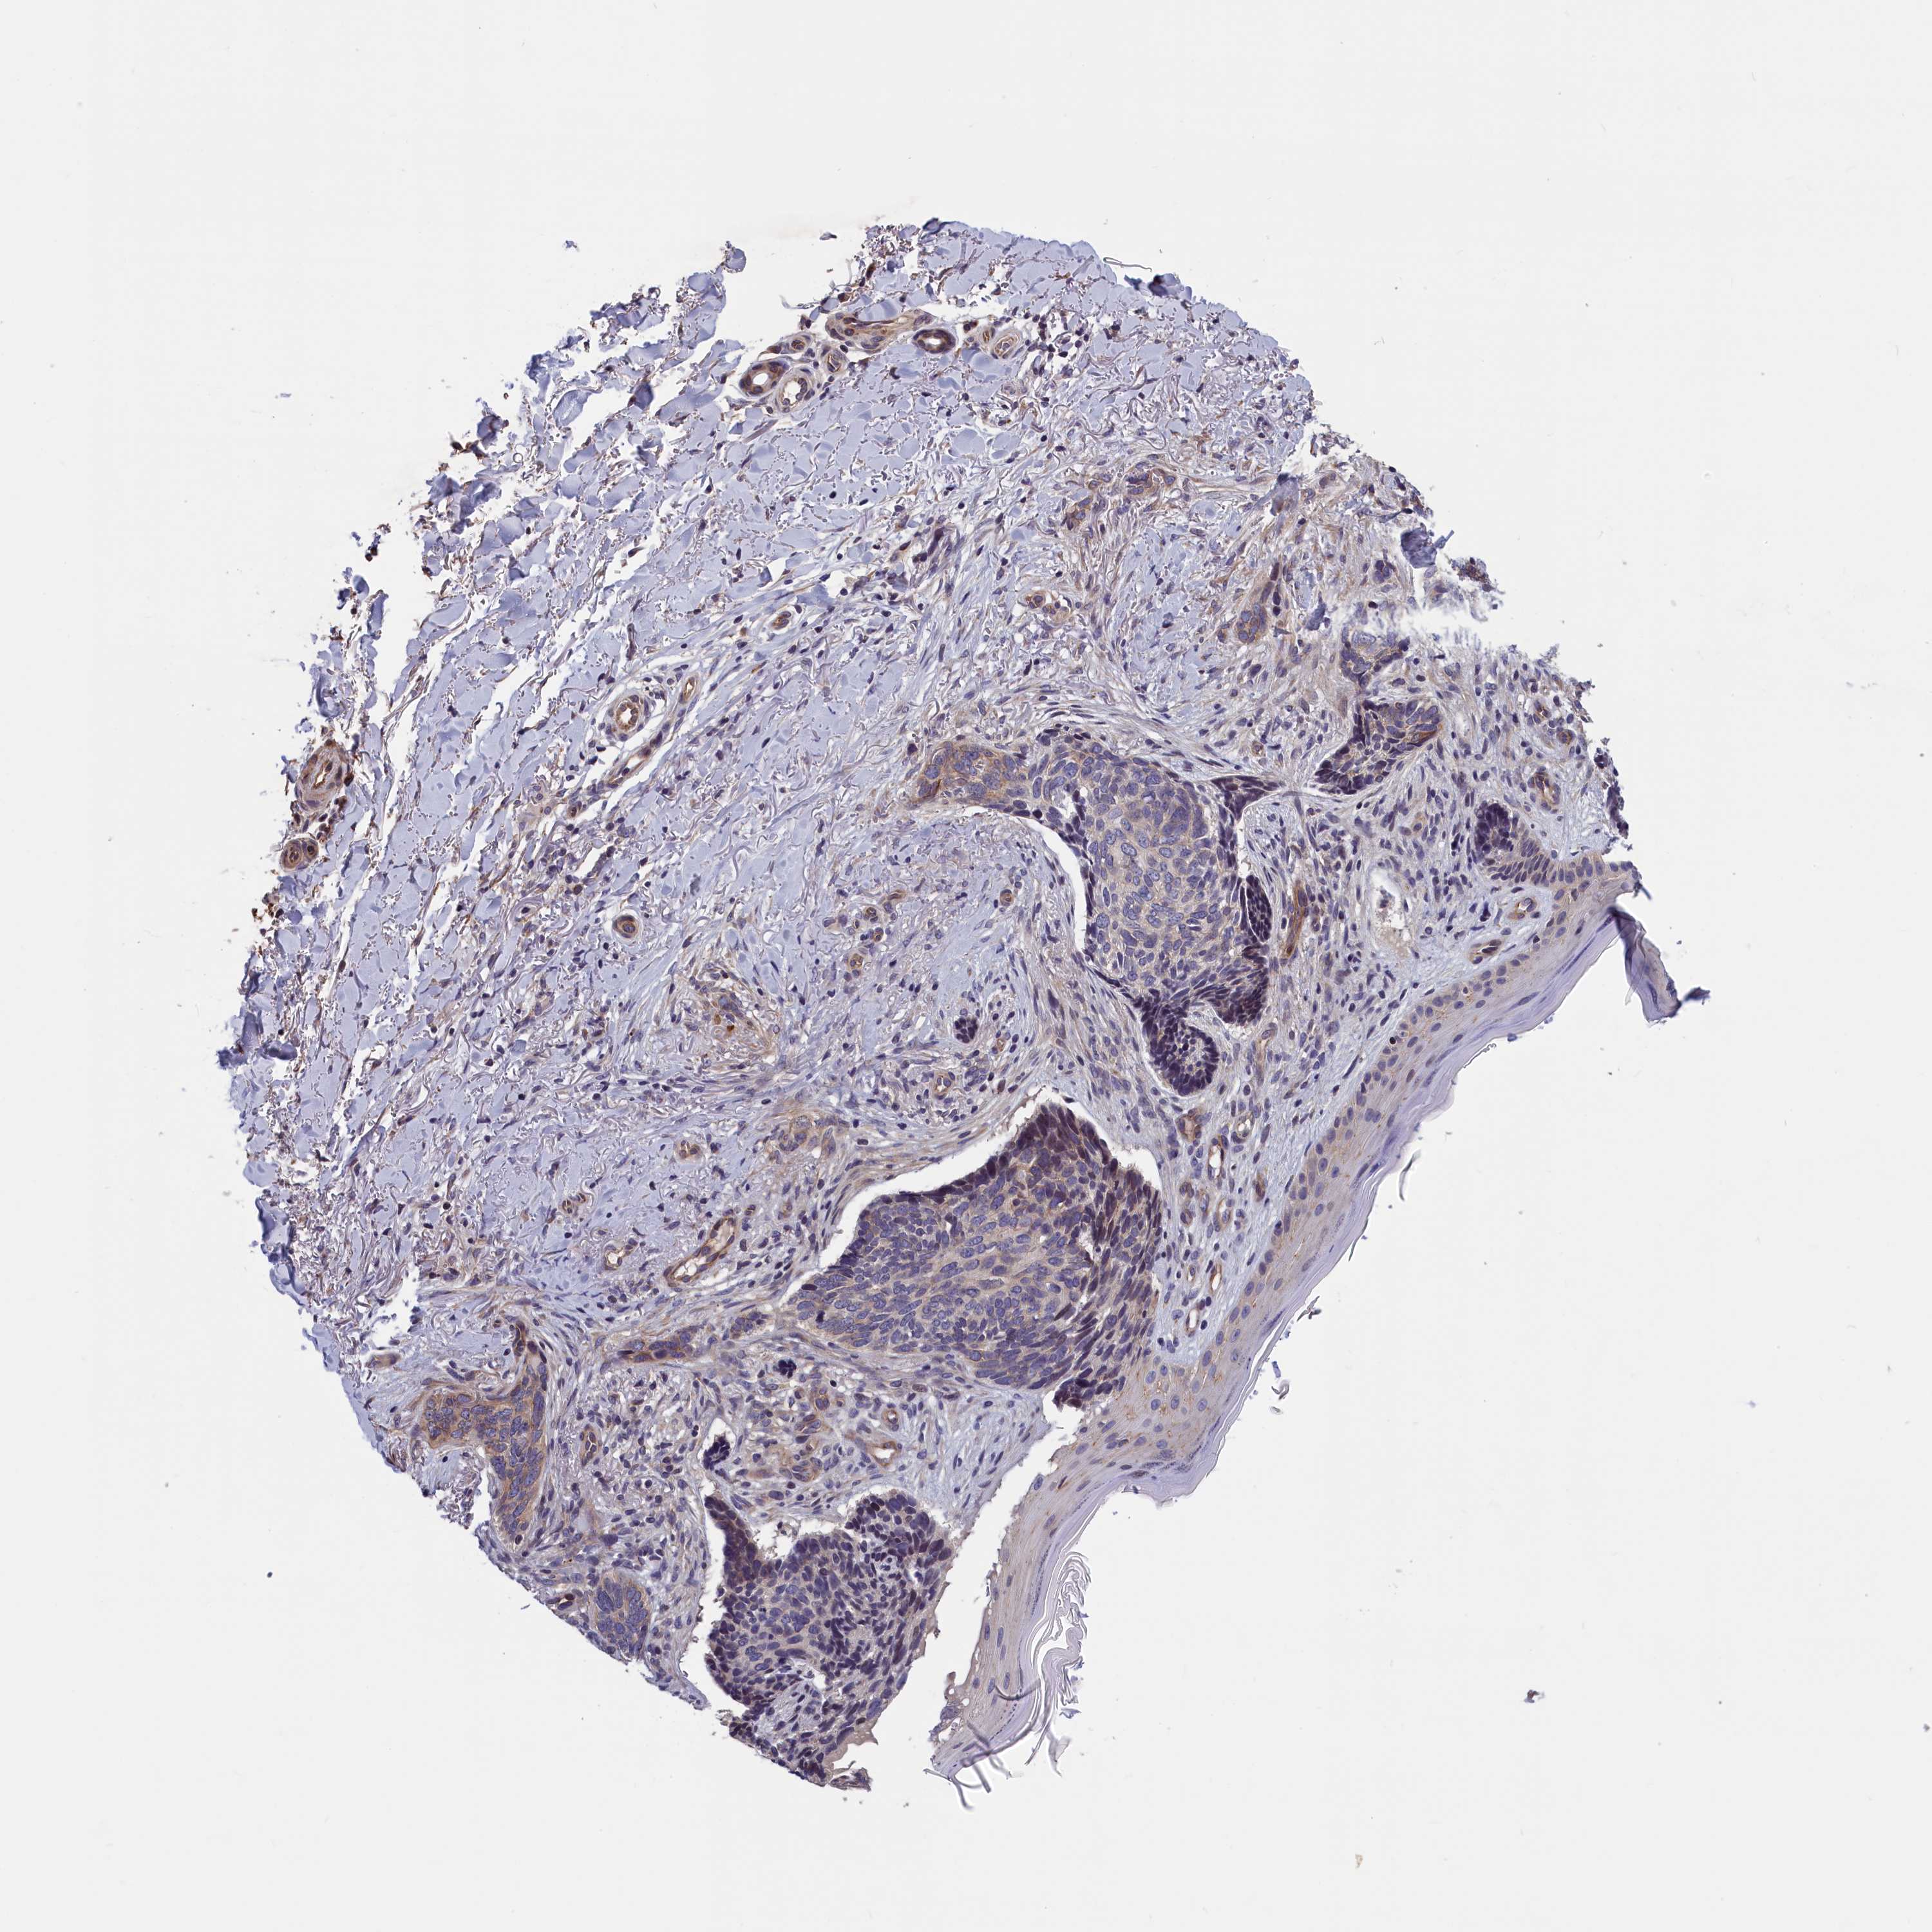

SKIN CANCER - Protein expressioni

A mouse-over function shows sample information and annotation data. Click on an image to view it in a full screen mode. Samples can be filtered based on level of antibody staining by selecting one or several of the following categories: high, medium, low and not detected. The assay and annotation is described here.

Each image is clickable and will lead to virtual microscopy that enables deeper exploration of all samples and also displays staining intensity scores, fraction scores and subcellular localization as well as patient and tissue information for each sample.

Antibody HPA040824

Staining

High

Medium

Low

Not detected

Intensity

Strong

Moderate

Weak

Negative

Quantity

>75%

75%-25%

<25%

None

Location

Nuclear

Cytoplasmic/membranous

Cytoplasmic/membranous,nuclear

Basal cell carcinoma

Squamous cell carcinoma, NOS